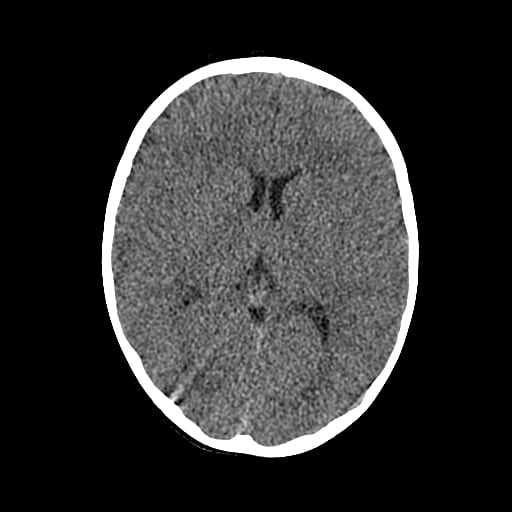

Age: 1

Sex: Male

Indication: Fall